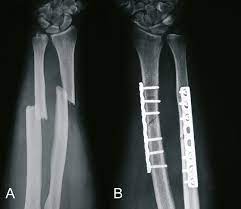

1 2 3 4 5 6. Hier ist die Radiusfraktur nicht mit einer Platte sondern mit Kirschnerdrähten erfolgt. Wenn nun diese Schrauben entfernt werden kann es passieren dass die Knochen dann keinen Halt mehr haben und auseinander oder zusammen fallen.

Orthoforum Unterarmfraktur

Ergebnisse Und Verlauf Von Unterarmschaftfrakturen Bei Erwachsenen Pdf Free Download